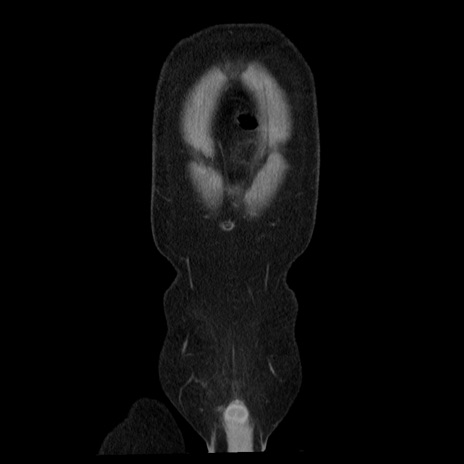

横断像

【症例】40歳代男性

【現病歴】2日前から胃痛あり。徐々に周期的な激痛に変化した。本日になっても激痛があるため受診。

【身体所見】意識清明、BT 38-39℃台あり、腹部:膨満、やや硬、右下腹部に圧痛あり。

【データ】WBC 8500、CRP 23.26